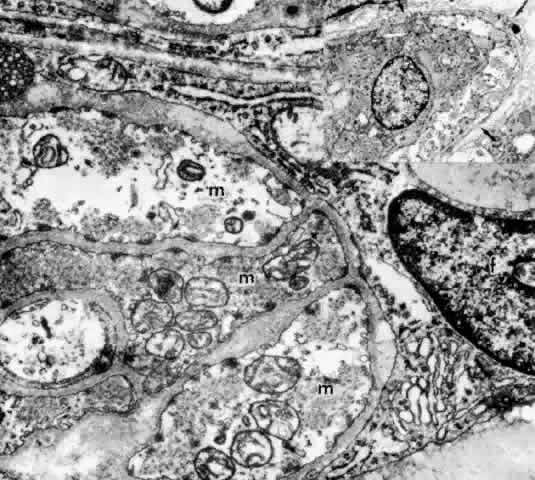

Fig. 16. Ciliary epithelium in the anterior pars plicata of a 19-year-old. Posterior

chamber surface (PC) of the nonpigmented epithelium (NPE) has a sawtooth

pattern seen irregularly throughout this layer with aging. Mitochondria (m) are

large, plentiful, and show artifactual hydropic change. Rough

endoplasmic reticulum is present below the nuclei (asterisk). Note

that the apices of the pigmented epithelial cells (PE) are conical, with

prolongations of NPE between them. (X 8320) Fig. 16. Ciliary epithelium in the anterior pars plicata of a 19-year-old. Posterior

chamber surface (PC) of the nonpigmented epithelium (NPE) has a sawtooth

pattern seen irregularly throughout this layer with aging. Mitochondria (m) are

large, plentiful, and show artifactual hydropic change. Rough

endoplasmic reticulum is present below the nuclei (asterisk). Note

that the apices of the pigmented epithelial cells (PE) are conical, with

prolongations of NPE between them. (X 8320)